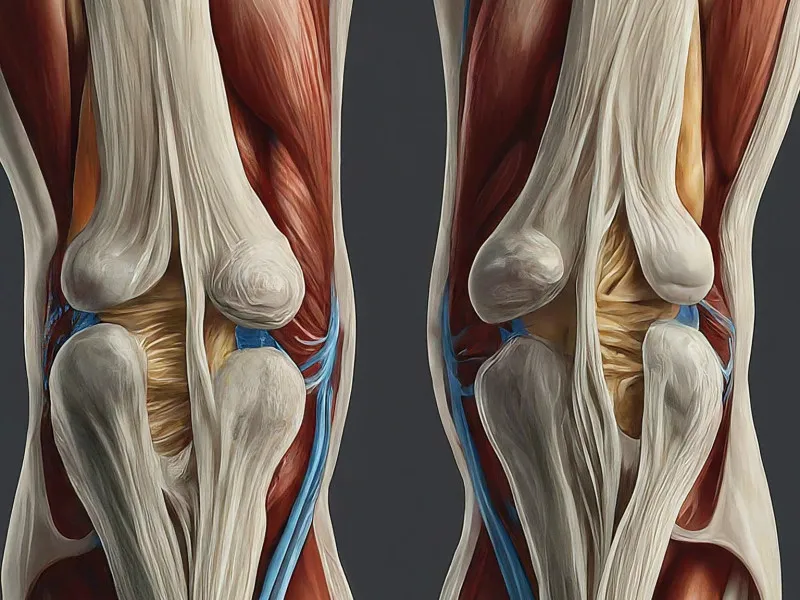

An anterior cruciate ligament (ACL) tear is a common knee injury that frequently affects athletes but can occur in anyone. The ACL is one of the four major ligaments of the knee that connect the thighbone to the shinbone. This ligament is crucial for stabilising the knee while twisting or turning. ACL tears are often caused by sudden stops, changes in direction, or landing awkwardly from a jump. Initial symptoms typically include a loud ‘pop’ noise, severe pain, swelling, loss of range of motion, and a feeling of instability. Diagnosing an ACL tear usually involves a physical examination, and confirmation often requires imaging tests like an MRI.

ACL tears can have profound impacts on different areas of an individual’s life. For athletes, it may mean a significant time away from their sports. The injury also increases the risk of future joint issues, such as osteoarthritis. Understanding the underlying anatomy and biomechanics of the knee helps in visualising how ACL injuries occur and can guide prevention strategies. Although ACL injuries can heal with rest and rehabilitation, severe tears often require surgery to restore knee stability and function.